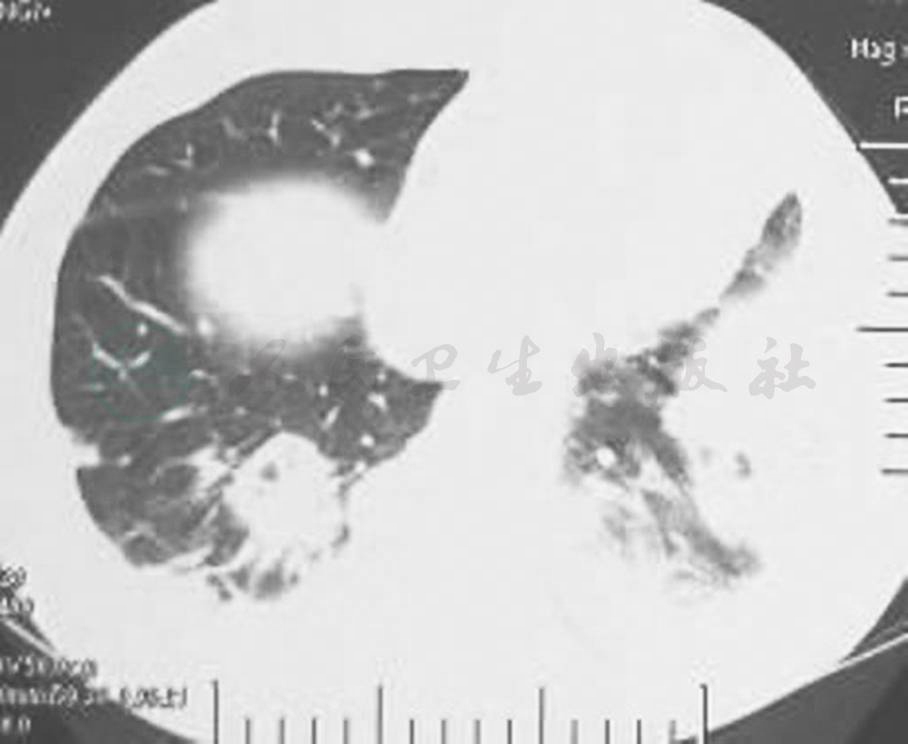

胸部CT示双肺多发结节、空洞影,左舌叶、右下叶大片渗出影(图1),一周后加重 (图2)。

图1 胸部CT表现(2011-8-10)

胸部CT显示双肺多发结节、空洞影,左舌叶、右下叶大片渗出影